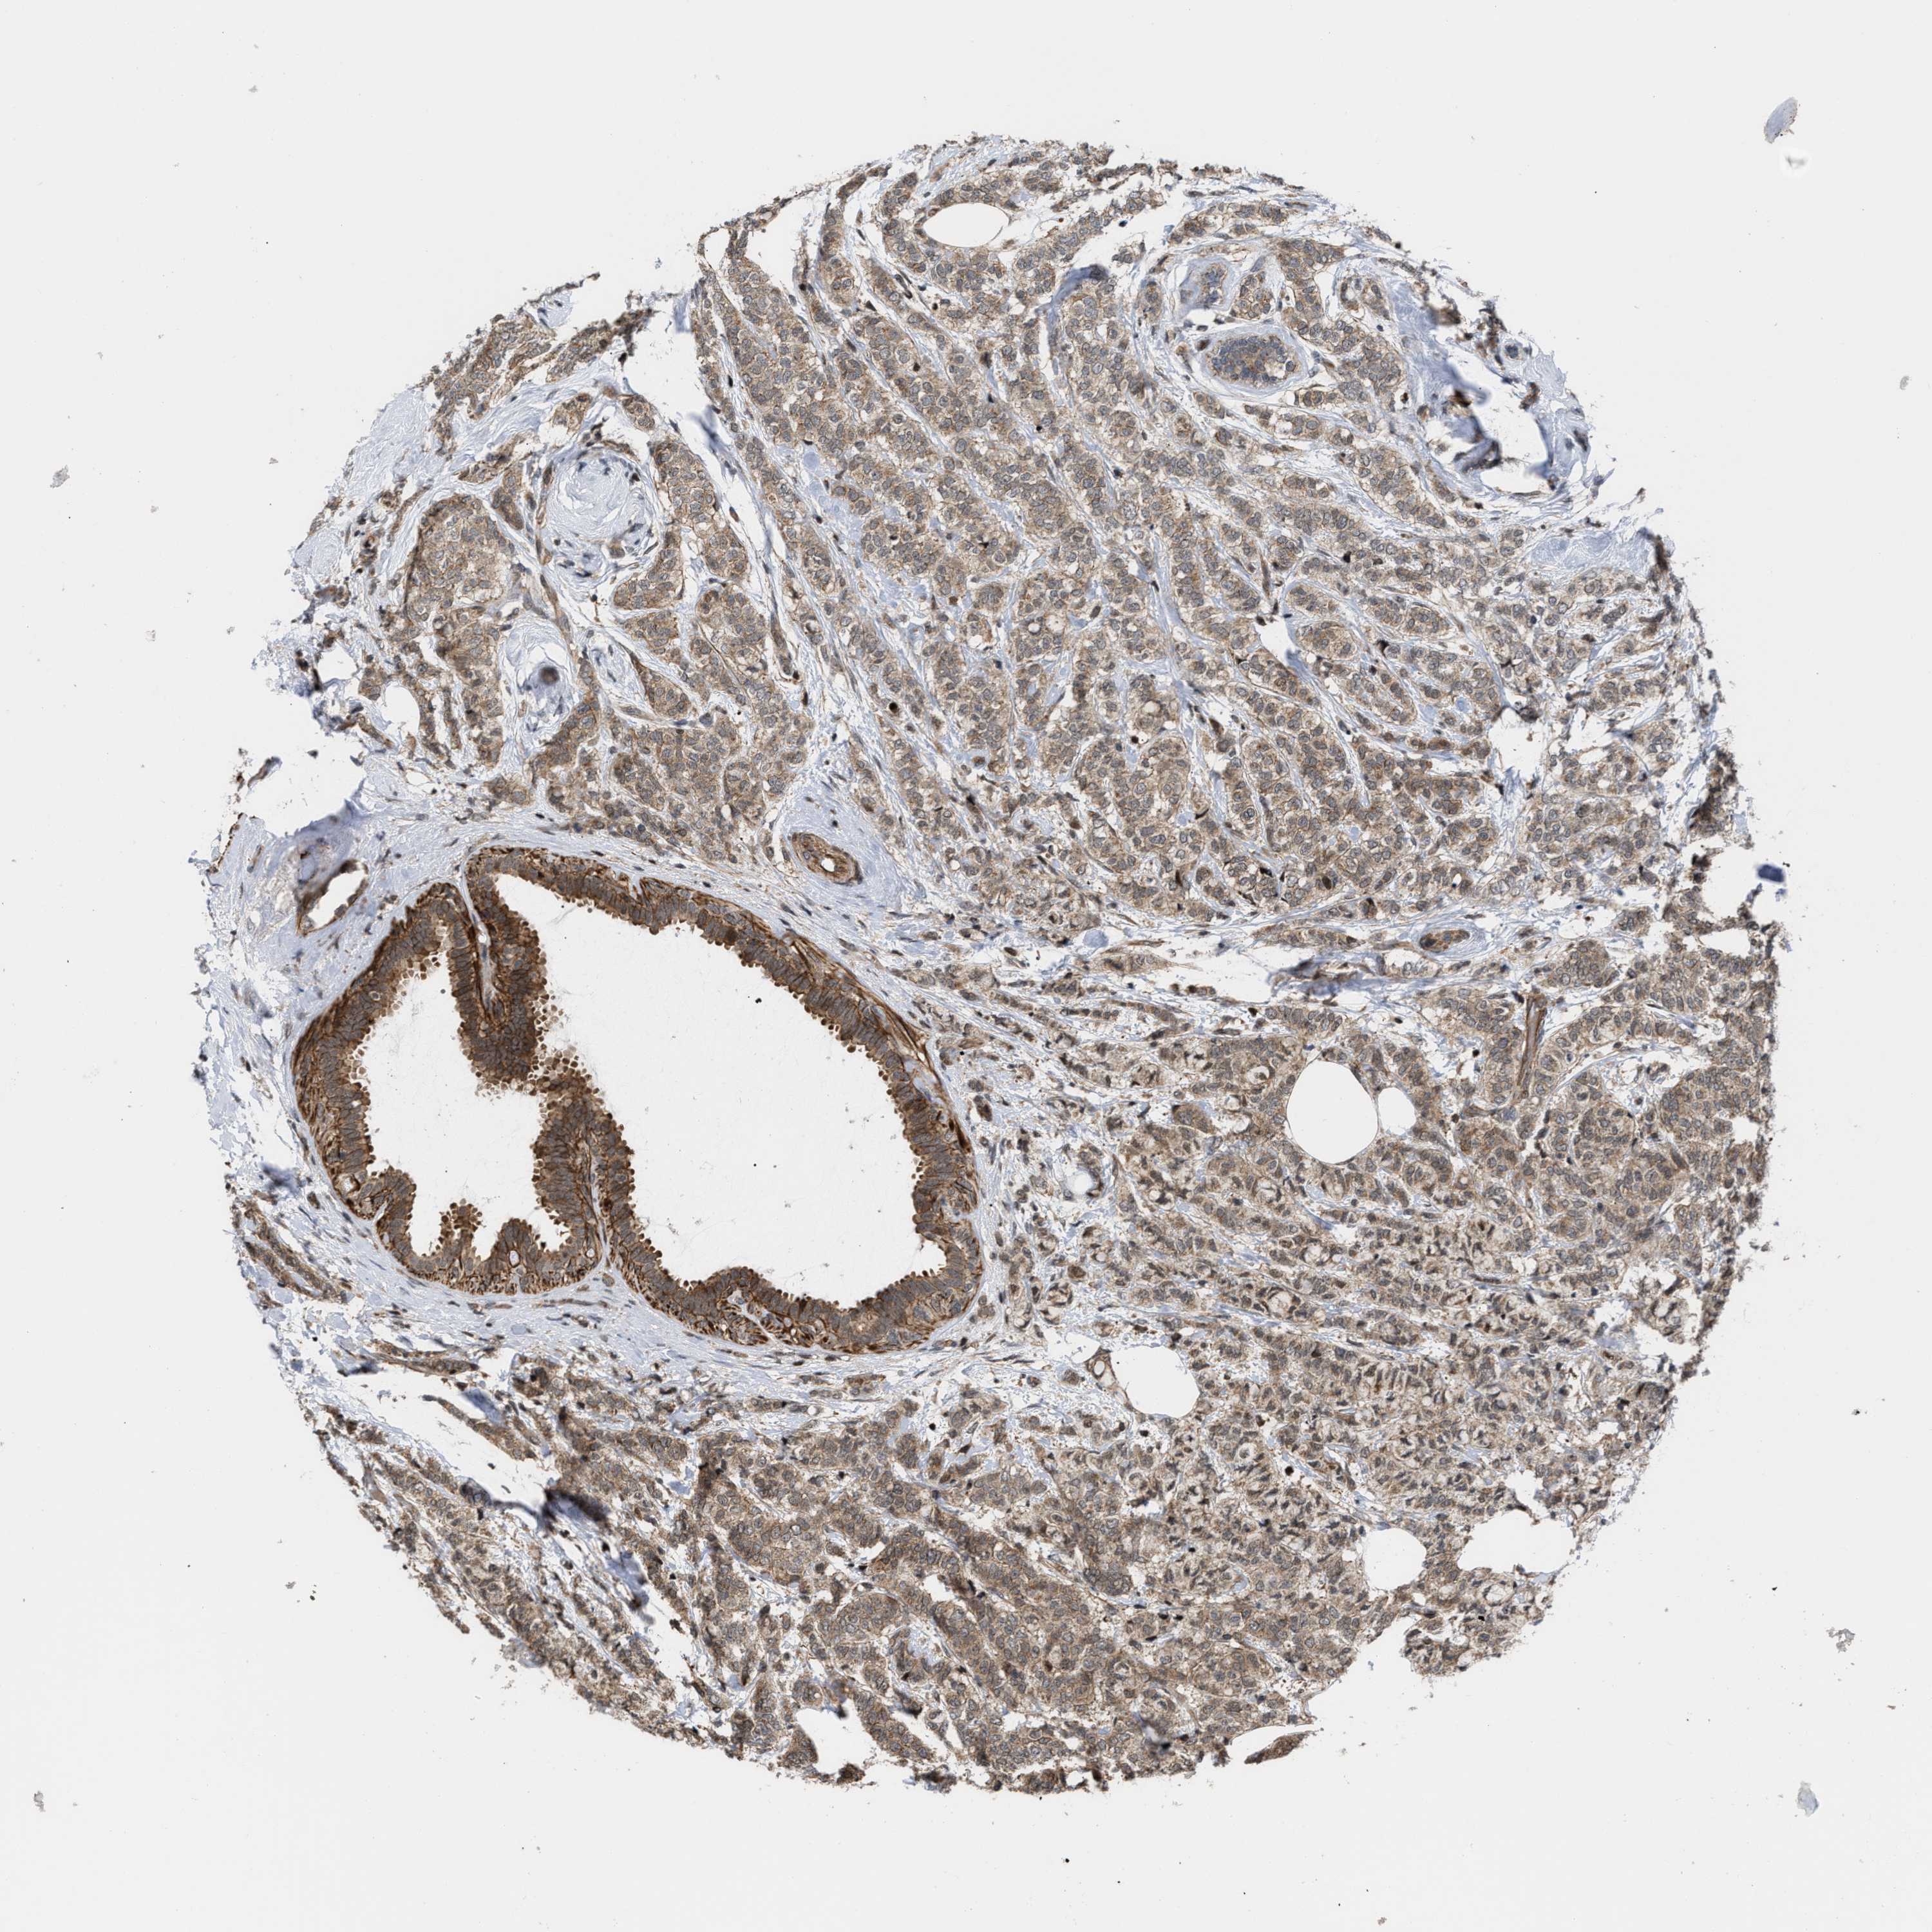

CANCER BREAST CANCER Show tissue menu

BRCA TCGA BRCA VALIDATION PROTEIN EXPRESSION